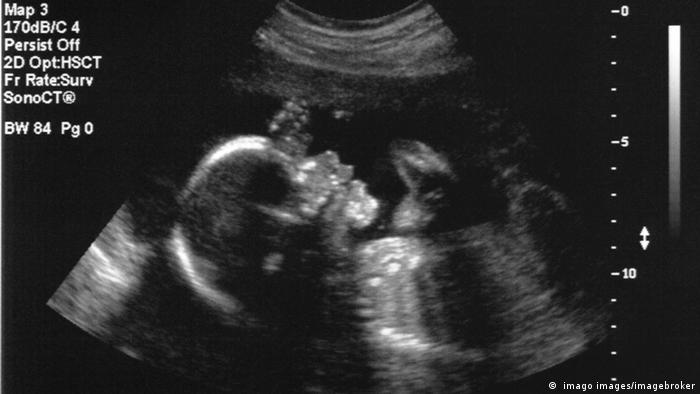

Con la ayuda de una ecografía, los doctores utilizaron una técnica quirúrgica llamada embolización para tratar una malformación de la vena de Galeno, una rara afección prenatal que afecta al cerebro y que suele tratarse después del nacimiento.